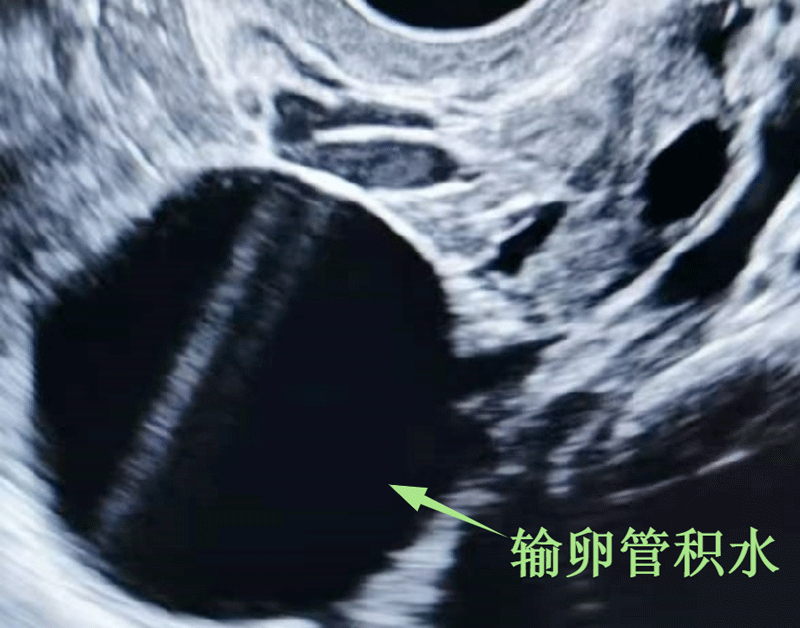

输卵管积水

输卵管积水指输卵管伞端阻塞导致输卵管渗出液积聚形成积液,多由输卵管炎、输卵管妊娠等引起,伴有痛经、月经失调、阴道分泌物增多。输卵管积液生育科普频道,2023整理更新输卵管积水严重程度、试管怀孕生育等生育知识,帮助人们获取输卵管积水试管成功了、输卵管积水竟然怀孕了等实用经验。